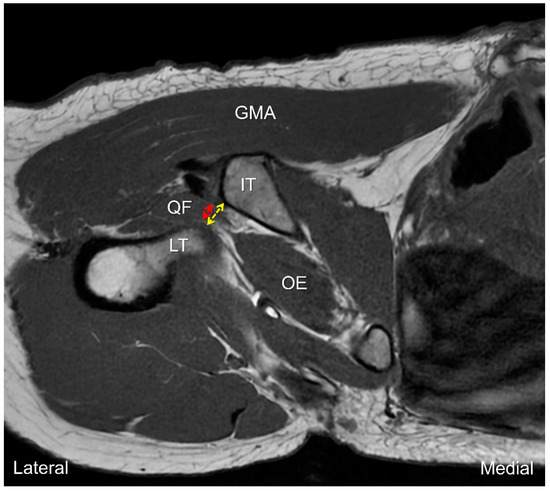

7. MRI Assessment

8. Dynamic Ultrasound Evaluation